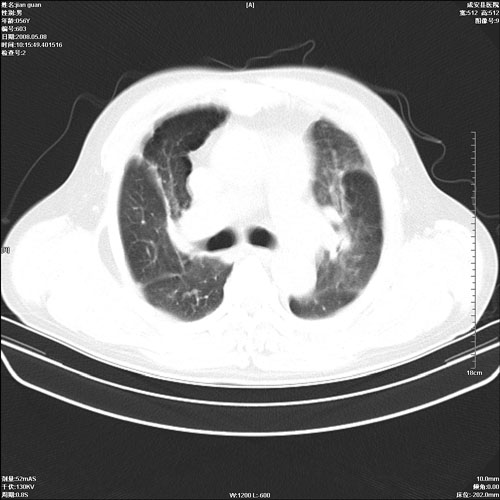

病人 男 60岁 主诉 胸闷 无明显发热 一般情况尚可。

两上肺陈旧性结核;慢支肺气肿、伴感染?

考虑1心功不全,肺水肿

2右上肺结核纤维性病灶、肺气肿

1.右上肺陈旧性肺结核.

2.心脏增大(以左心室增大为著),请结合b超及听诊.

1.两上肺陈旧性结核;慢支肺气肿。

2.肺门血管扩张,心脏增大,为肺心病

考虑.两上肺陈旧性结核;慢支肺气肿。肺心病

两上肺陈旧性结核;慢支肺气肿。肺肺间质纤维化

1.陈旧肺结核;

2.慢支肺气肿;

3.肺心病.